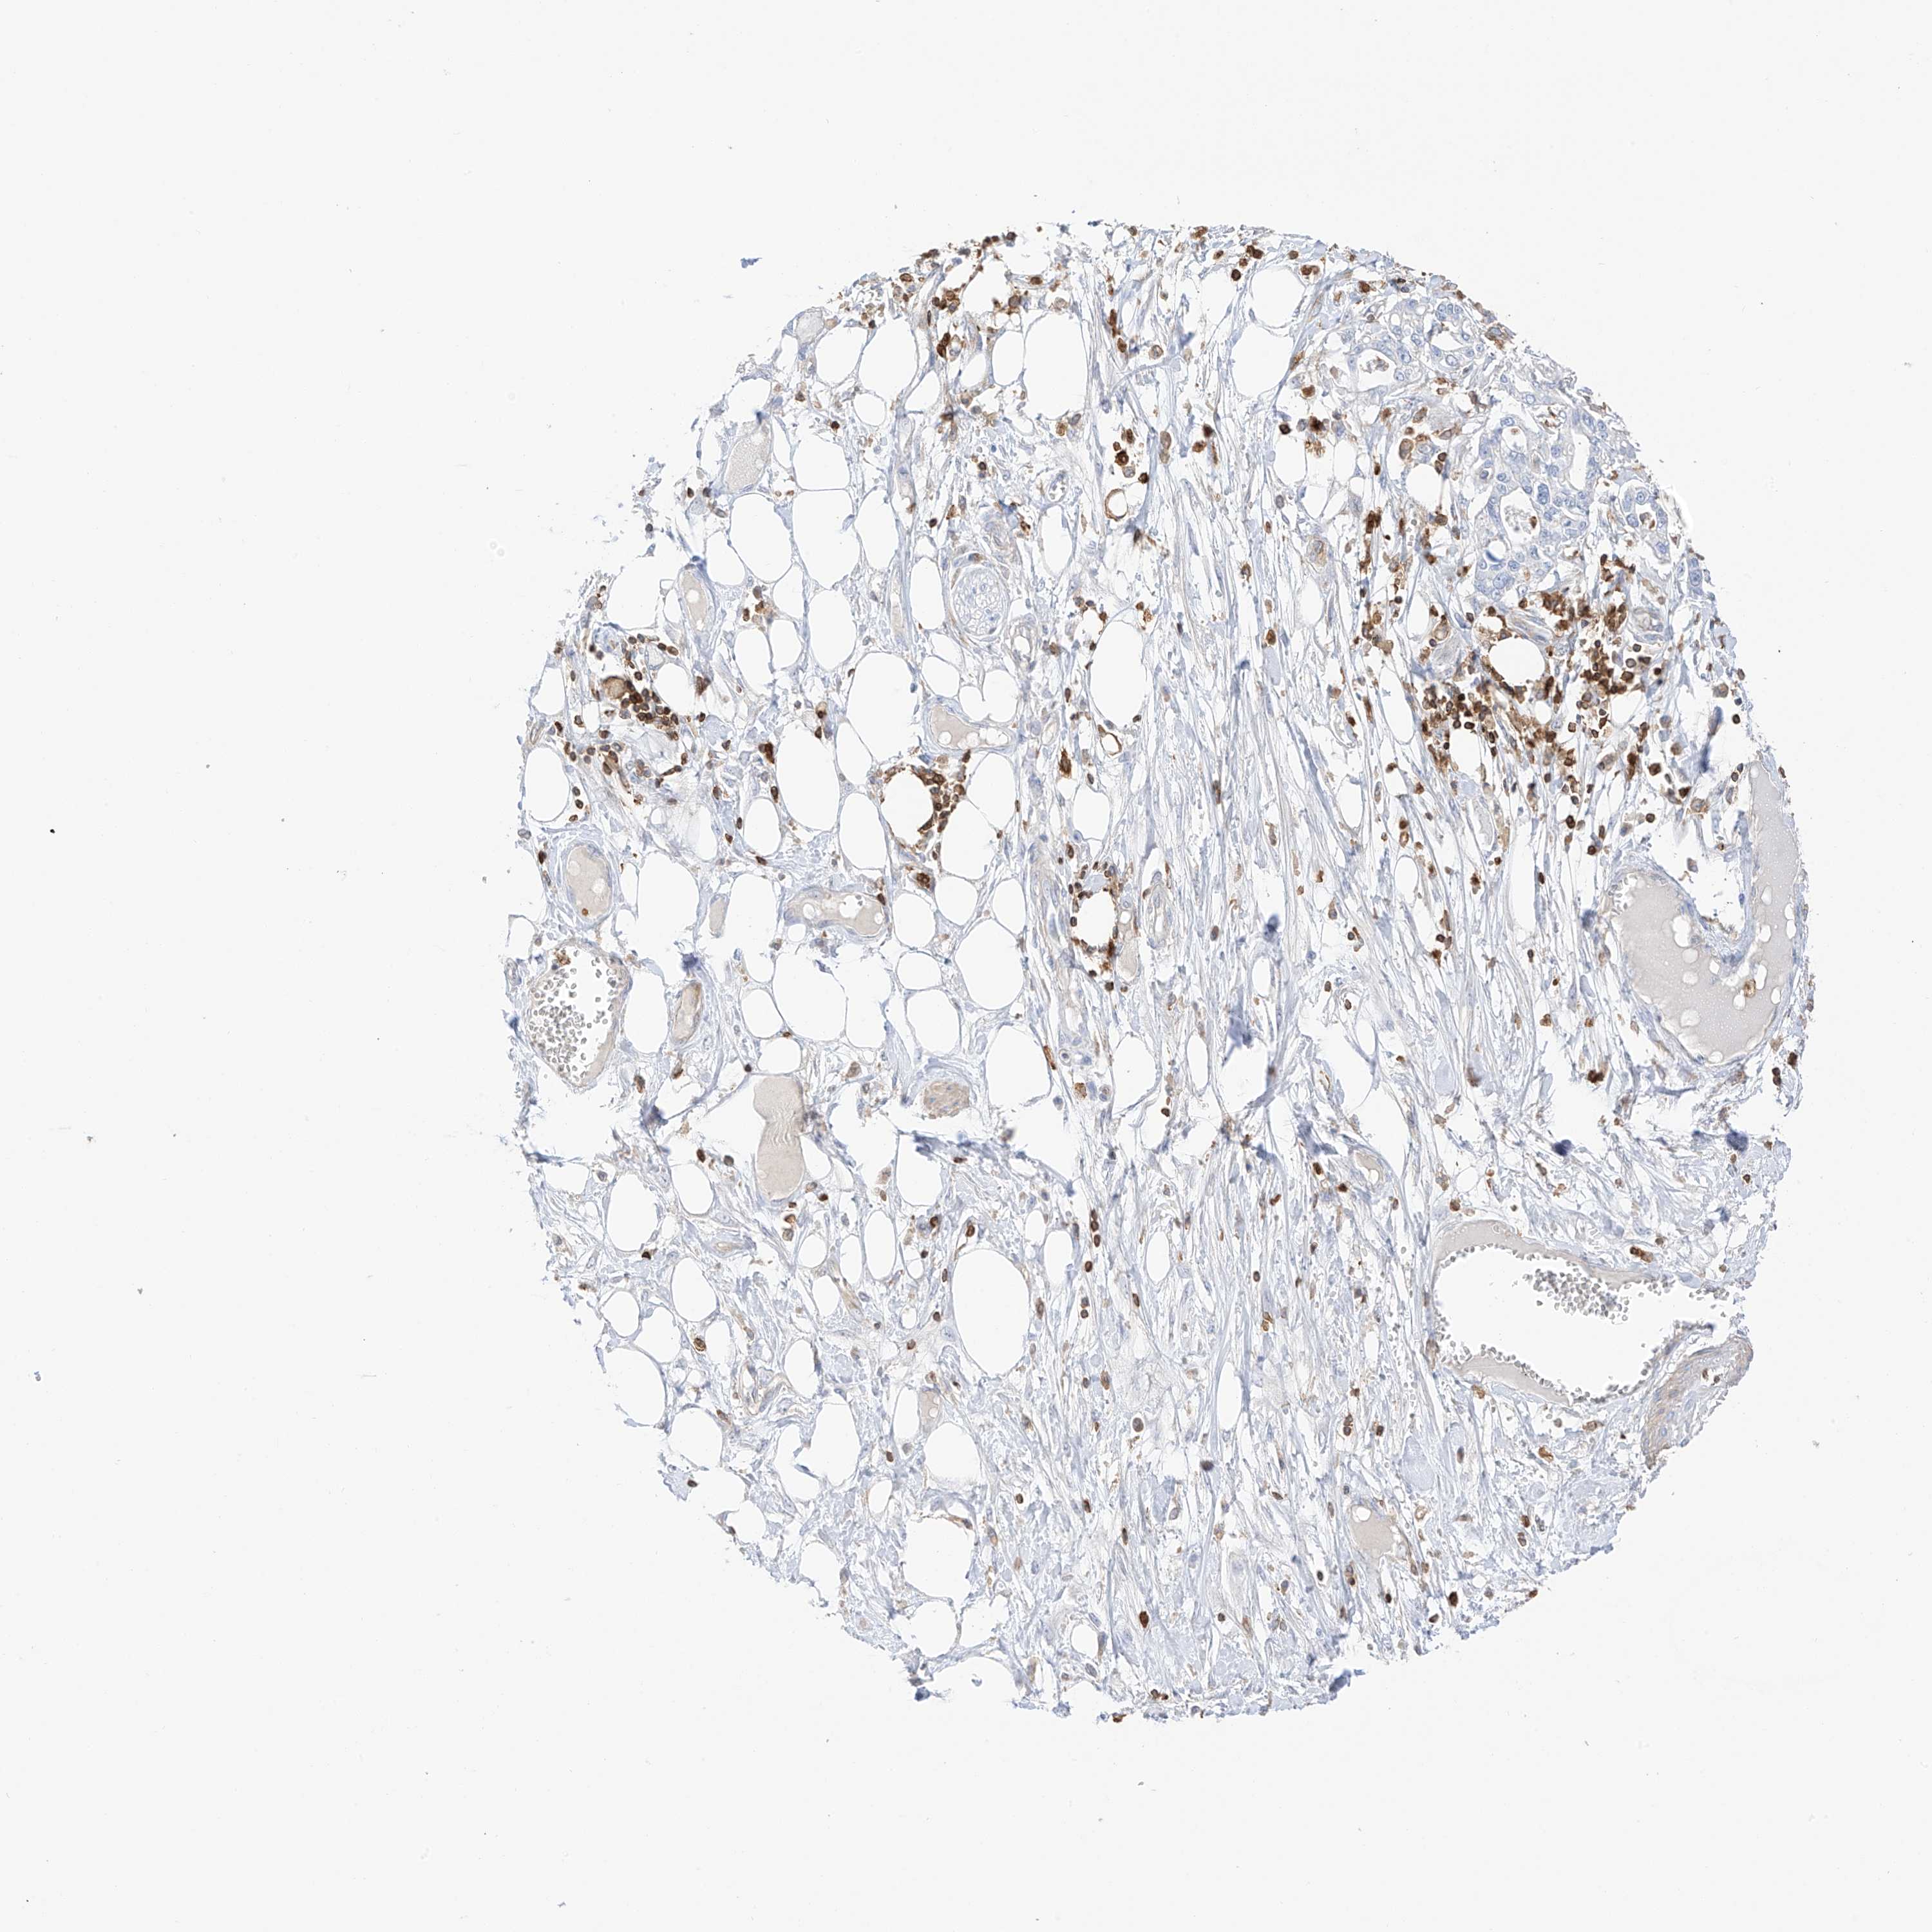

PANCREATIC CANCER - Protein expressioni

A mouse-over function shows sample information and annotation data. Click on an image to view it in a full screen mode. Samples can be filtered based on level of antibody staining by selecting one or several of the following categories: high, medium, low and not detected. The assay and annotation is described here.

Note that samples used for immunohistochemistry by the Human Protein Atlas do not correspond to samples in the TCGA dataset.

Antibody stainingi

Antibody staining in the annotated cell types in the current human tissue is reported as not detected, low, medium, or high, based on conventional immunohistochemistry profiling in selected tissues. This score is based on the combination of the staining intensity and fraction of stained cells.

Each image is clickable and will lead to virtual microscopy that enables deeper exploration of all samples and also displays staining intensity scores, fraction scores and subcellular localization as well as patient and tissue information for each sample.

Antibody HPA035346

Antibody HPA061395

Staining

High

Medium

Low

Not detected

Intensity

Strong

Moderate

Weak

Negative

Quantity

>75%

75%-25%

<25%

None

Location

Nuclear

Cytoplasmic/membranous

Cytoplasmic/membranous,nuclear

Adenocarcinoma, NOS